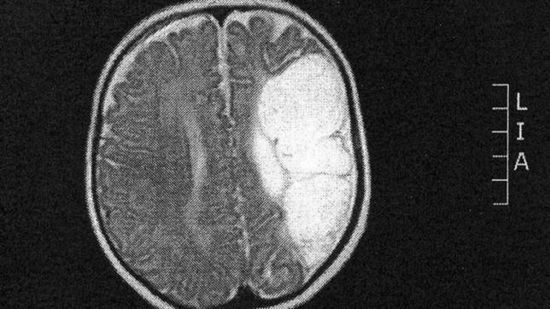

當我們看到傑克・格萊斯頓的時候,我們不會想到,眼前這個小男孩只有半個大腦是可以活著的。當他只有六個月大的時候,醫生們就發現了這個異常現象,並提醒孩子的父母他長大後可能無法走路,無法說話。然而,傑克卻打破了這個預言。現在已經肆歲的他完全可以像其他孩子那樣正常的生活。“這實在不可思議”,孩子母親薩拉表示。

傑克在嬰兒期時拍攝X光照片顯示,孩子的大腦只有壹半能夠進行活動,所有人都認為他不可能正常的成長。但是事情並沒有想他們想的那樣糟糕,傑克長的很壯實,身體健康,也可以像其他同齡孩子那樣正常的奔跑。“這太神奇了。”孩子的家人對此也感到很驚喜。

醫生表示,傑克這種病在醫學上講是腦軟化,並認為這壹半的大腦不會再生長。醫生將這種情況歸咎於子宮受到沖擊導致的氧氣不足,但是幸運的是這個孩子並沒有缺少基本的生理功能,仍然可以正常的走路和說話。當然盡管這樣,傑克還是時時需要有家人的看護,並且吃飯穿衣都需要幫助。- 新聞來源於其它媒體,內容不代表本站立場!